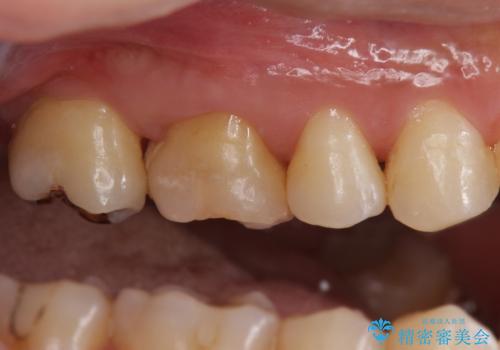

不適な樹脂の詰め物 被せ物で被覆

- 奥歯の劣化・変色した樹脂の詰め物をやり直していきます。

セラミックのインレーでは強度に不安が残るため、セラミッククラウンで全体を被覆することとしました。